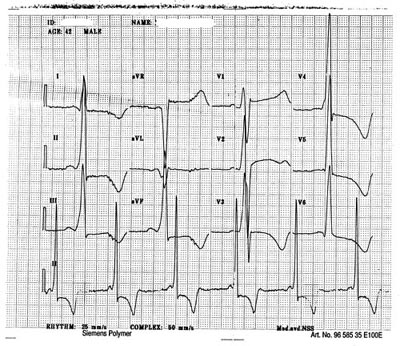

Pasient 1. 42 år gammel mann som i barneårene var plaget av episoder med smerter i hender og føtter, ledsaget av feber. Fra tenårene hadde han teleangiektasiliknende utslett spesielt på truncus. Han ble henvist til en universitetsklinikk 17 år gammel og fikk diagnosen sannsynlig angiokeratoma Mibelli. I voksen alder utviklet han varicer, og han ble operert for dette 35 år gammel. Fra 34 års alder hadde han lett proteinuri (påvist ved strimmel, ikke kvantifisert), periodevis deklive ødemer og lett avtakende nyrefunksjon (bedømt ut fra serum-kreatininverdi). I mange år hadde han perioder med diaré og imperiøs avføringstrang. Han ble henvist til medisinsk poliklinikk med spørsmål om sammenheng mellom utslett og nyresykdom. Før han ble tilbudt time, ble han innlagt tiltrengende øyeblikkelig hjelp pga. erysipelas som ikke hadde vist bedring ved behandling med penicillin peroralt. Ved innleggelsen hadde han et utslett karakteristisk for Fabrys sykdom, hypoalbuminemi og et patologisk EKG med kort PQ-tid (94 ms) og tegn til venstre ventrikkel-hypertrofi med repolarisasjonsforstyrrelser (fig 1). Under oppholdet ble det påvist proteinuri på 0,7g/døgn. Ekkokardiografisk var det venstre ventrikkel-hypertrofi med obstruksjon av venstre ventrikkels utløpstractus (intrakavitær gradient 25 mm Hg), systolisk anterior bevegelse av mitralklaffen og en liten mitralinsuffisiens. Blodprøve viste betydelig redusert alfagalaktosidase-aktivitet (3,37 µ kat/kg protein i leukocytter, referanseområde 17,7 – 26,4 µ kat/kg) (Mølndal sykehus, Sverige) og tynntarmsbiopsi avslørte lipidavleiringer submukøst; det første diagnostisk for, det andre vel forenlig med Fabrys sykdom. Pasientens nyrefunksjon var i nedre normalområde med en kreatininclearance på 1,2 ml/s/1,73 m2 (referanseområde 1,2 – 2,5 ml/s/1,73 m2). I løpet av tre års poliklinisk oppfølging har de kardiale funn vært uendret og nyrefunksjonen bedømt ut fra kreatininclearance stabil. Proteinutskilling i urinen har økt noe – til 4,0 g/døgn ved siste kontroll. Oftalmologisk undersøkelse har avdekket forandringer klassisk for Fabrys sykdom med cornea verticillata og linsefortetning i bakre skål.